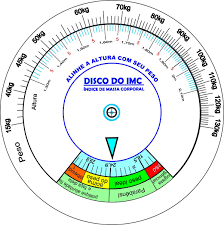

678 × 518 - gimolimpo.com

{"cb":15,"id":"jpp4X3OVBi6CfM:","isu":"gimolimpo.com","itg":0,"ity":"jpg","oh":518,"ou":"http://www.gimolimpo.com/PAGINA%2040/Castup_tv%20-%20The%20largest%20streaming%20platform%20for%20live%20streaming%20,%20live%20broadcasting%20and%20more___archivos/fondo_dieta_3.jpg","ow":678,"pt":"fondo_dieta_3.jpg","rid":"fqzWY27NIw7kDM","rmt":0,"rt":0,"ru":"http://www.gimolimpo.com/PAGINA%2040/INDICE%20MASA%20CORPORAL.htm","s":"Se

considera que una persona tiene un peso normal cuando tiene un índice

de masa corporal inferior a 25, entre 20 y 24 para las mujeres y entre

20 y 25 para

...","sc":1,"th":196,"tu":"https://encrypted-tbn0.gstatic.com/images?q\u003dtbn:ANd9GcTNxN-cKcd-O4XYTNYStZff7LMytZn8CAb7XGv9aZCsd9KEqRF4vw","tw":257}

350 × 225 - gimolimpo.com

{"id":"eD7cRRkVLMiQpM:","isu":"gimolimpo.com","itg":0,"ity":"jpg","oh":225,"ou":"http://www.gimolimpo.com/PAGINA%2029/Tabla_IMC.jpg","ow":350,"pt":"gim

olimpo","rid":"PDBNppOb_qodpM","rmt":0,"rt":0,"ru":"http://www.gimolimpo.com/PAGINA%2029/I%20M%20C.htm","s":"Hoy

habia 451 Visitantes (2439 número de aciertos) ¡Aqui en esta

página!","sc":1,"th":180,"tu":"https://encrypted-tbn0.gstatic.com/images?q\u003dtbn:ANd9GcQ4hZv433jUY5siYozITKpARz0jX6WrzceI_YJgTLwkbHfpdYGD","tw":280}